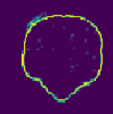

Despite the state-of-the-art performance for medical image segmentation, deep convolutional neural networks (CNNs) have rarely provided uncertainty estimations regarding their segmentation outputs, e.g., model (epistemic) and image-based (aleatoric) uncertainties. In this work, we analyze these different types of uncertainties for CNN-based 2D and 3D medical image segmentation tasks. We additionally propose a test-time augmentation-based aleatoric uncertainty to analyze the effect of different transformations of the input image on the segmentation output. Test-time augmentation has been previously used to improve segmentation accuracy, yet not been formulated in a consistent mathematical framework. Hence, we also propose a theoretical formulation of test-time augmentation, where a distribution of the prediction is estimated by Monte Carlo simulation with prior distributions of parameters in an image acquisition model that involves image transformations and noise. We compare and combine our proposed aleatoric uncertainty with model uncertainty. Experiments with segmentation of fetal brains and brain tumors from 2D and 3D Magnetic Resonance Images (MRI) showed that 1) the test-time augmentation-based aleatoric uncertainty provides a better uncertainty estimation than calculating the test-time dropout-based model uncertainty alone and helps to reduce overconfident incorrect predictions, and 2) our test-time augmentation outperforms a single-prediction baseline and dropout-based multiple predictions.